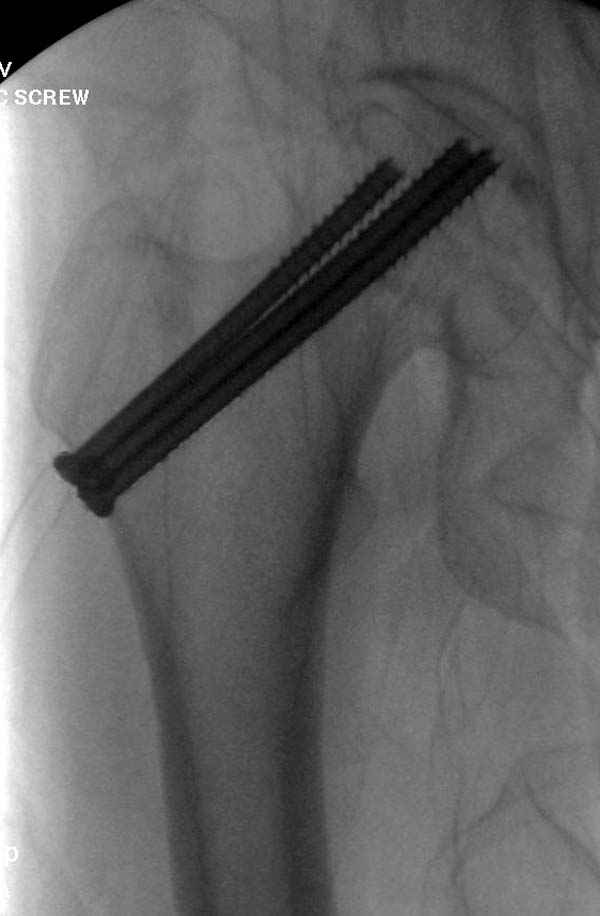

Профилактику дальнейшего раскола неполного перелома шейки провели тремя канюлированными шурупами.

На второй день после выписки упал дома. Снимки приложены. Коллеги рекомендуют удаление шурупа и вытяжение. Что делать?

Правильно, ситуация изменилась, как говорят у нас теперь "different animal", надо решать проблему подвертельного перелома. При наличии различных вариантов фиксаторов, включая Страйкер Гамма 3, мы выбрали DePuy Antegrade Trachanteric Nail из-за многовариантности проксимальной фиксации и двойного изгиба. Вводится через вертел под 8 градусным углом, и есть достаточный передний диафизарный изгиб, предупреждающий пенетрацию дистального переднего кортекса.